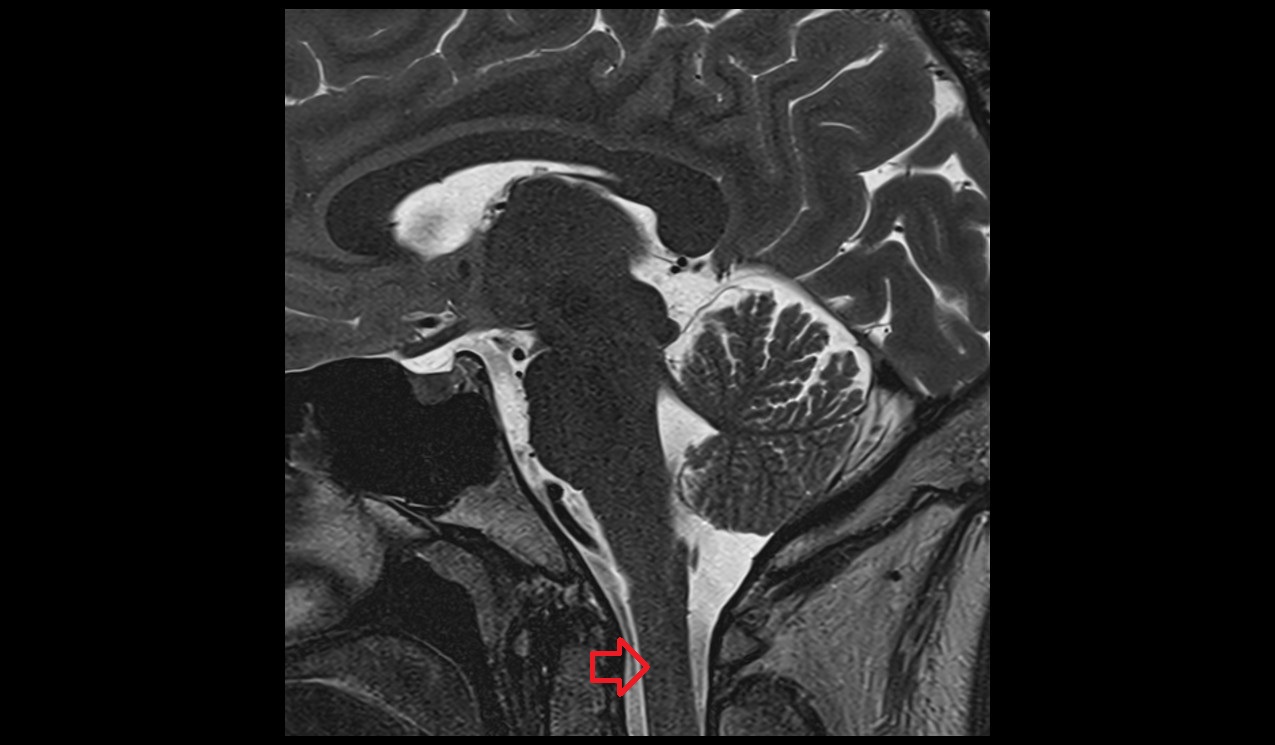

- Uterus

- Cervix of uterus

- Vagina

- Endometrium of uterus

- Myometrium of uterus

- Junctional zone of uterus